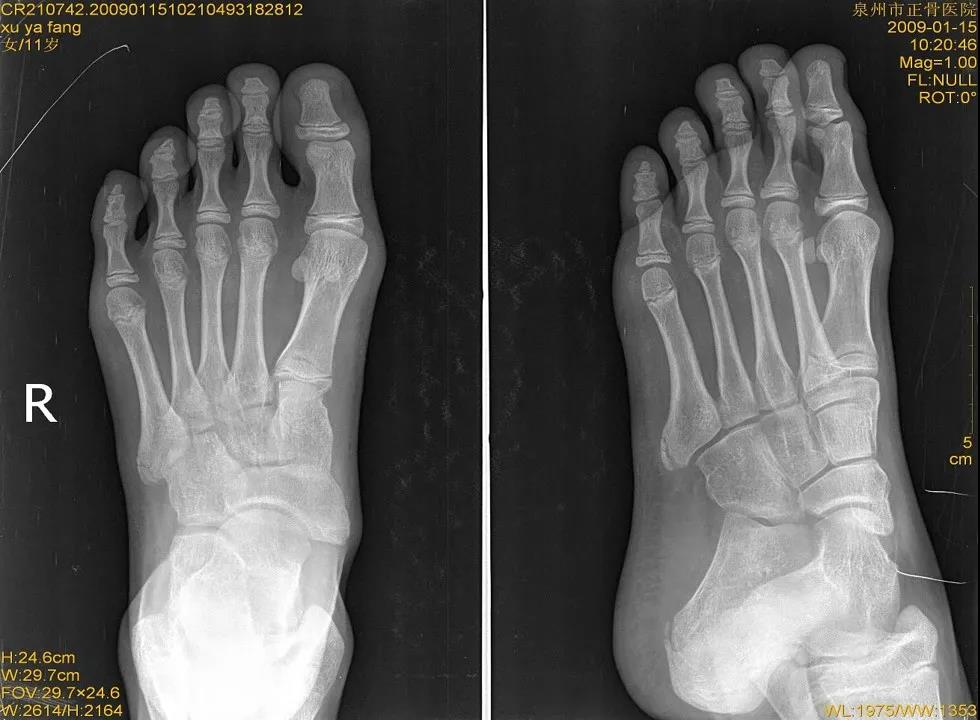

X线

儿童骨骺未闭

儿童正常骨骺